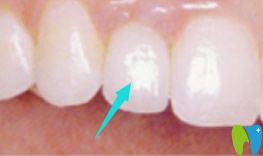

醫(yī)生給我采用萬(wàn)翔口腔的微創(chuàng)種植技術(shù)種了一顆門牙,大家看看效果如何?和真牙沒(méi)有任何區(qū)別?,F(xiàn)在我說(shuō)活終于是不露氣兒了。

種植了牙齒后,我變得開(kāi)朗了,也自信了,不像門牙缺失的時(shí)候,根本不敢張嘴笑。個(gè)人覺(jué)得牙齒缺失真的很影響形象和自尊。萬(wàn)翔口腔溫馨提示:無(wú)論是單顆牙或多顆牙缺失的朋友,都可以通過(guò)種植牙齒來(lái)改善!